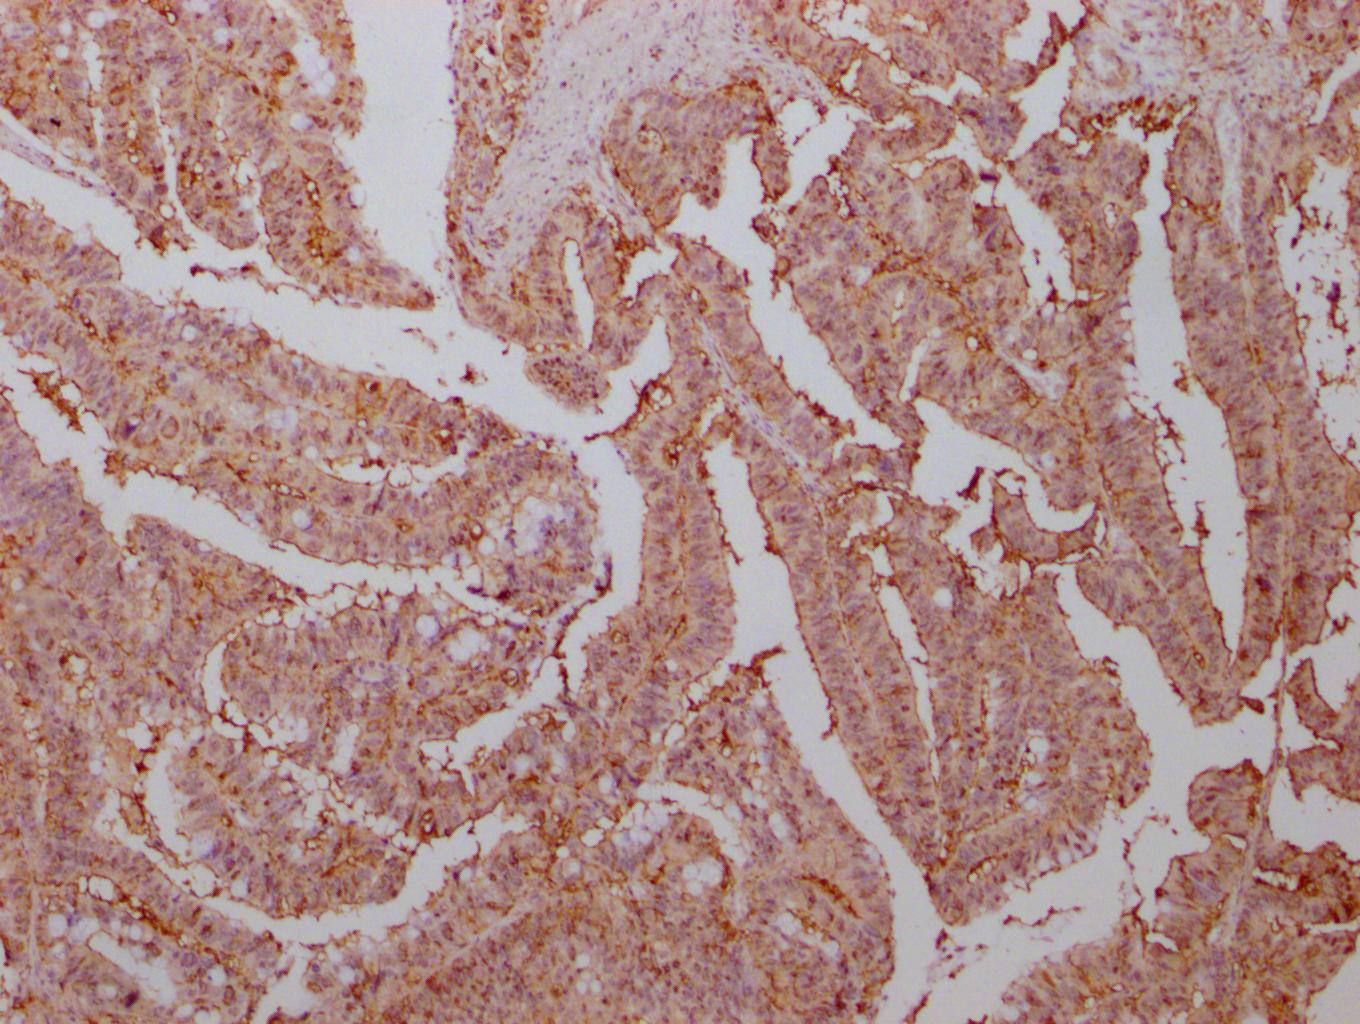

IHC image of CSB-MA007670A0m diluted at 1:500 and staining in paraffin-embedded human liver cancer tissue performed on a Leica BondTM system. After dewaxing and hydration, antigen retrieval was mediated by high pressure in a citrate buffer (pH 6.0). Section was blocked with 10% normal goat serum 30min at RT. Then primary antibody (1% BSA) was incubated at 4°C overnight. The primary is detected by a biotinylated secondary antibody and visualized using an HRP conjugated SP system.

-